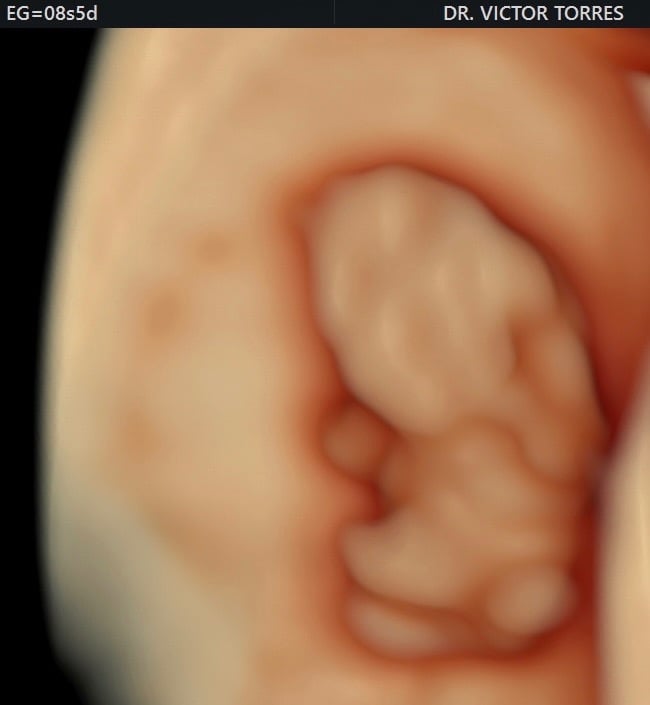

Monitoreo y cuidado especializado para el bienestar de tu bebé durante el embarazo.

Desde sus primeros latidos, brindamos el mejor cuidado para un comienzo saludable y seguro.

Galería Neomamá

Explora momentos especiales y servicios para mamás y bebés aquí.